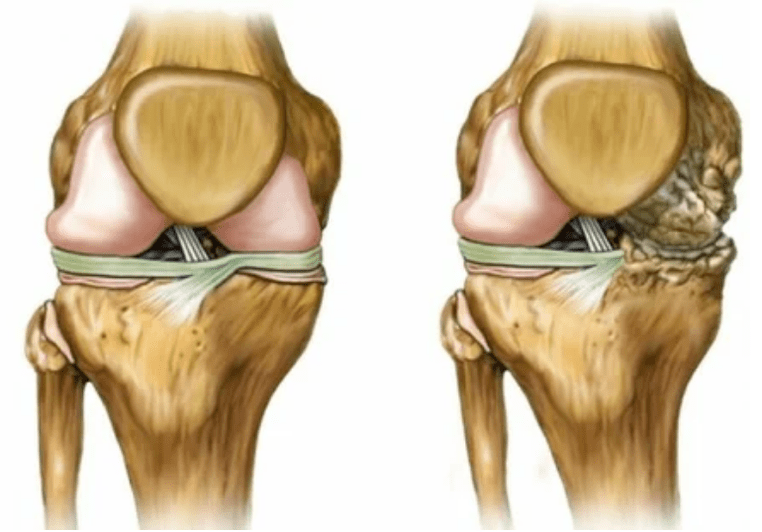

- Gradu 1. Nahaste morfologikoak dagoeneko hasi dira, baina oraindik ez dira nabaritzen. Patologiak fluido sinovialen egoerari eragiten dio batez ere, eta horrek okerrago hornitzen ditu kartilagoko ehunak mantenugaien osagaiekin, kartilagoaren indarra murriztuz. Artikulazioen karga hantura eta mina eragiten du.

- 2. etapa. Hornikuntzaren gabezia dela eta, beharrezko kartutxoak suntsitzen dira, hezur-hazkuntzak kartilagoaren gainazalean eratzen dira. Minak pertsonaia nabarmenagoa eskuratzen du, atseden luzea egin ondoren, lan fisiko txikiak ezabatzen ditu. Mina hanturarekin batera doa. Muskuluak luzatuta daude, eta horrek motor motordun ahulak edo batez bestekoak eragiten ditu.

- 3 gradu. Askotan minak daude, zaila da gorputz-adarra mugitzea artikulazioan izandako aldaketengatik. Lesioak zabalak dira, biluzik begiratzen dute. Gune bateratuaren deformazioa gertatzen da, kaltetutako eremua puztu eta gorria bihurtzen da. Gorputz ardatza asaldatuta dago eta horrek mugimenduaren konplexutasuna dakar. Aldaketa patologikoak ligamenduak laburtzea eragiten du. Subluekiak eta kontratazioak agertzen dira. Inguruko muskuluak laburtu edo luzatu egiten dira, eta horietatik kontratuaren funtzioa ahultzen da.